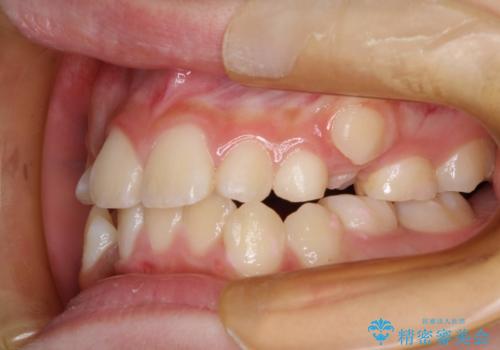

矯正歯科治療 → 叢生(でこぼこ・八重歯)

インビザラインによるガタつきの矯正治療 シンプル・短期間

犬歯のねじれ 下の歯のがたがた インビザラインで

前歯のがたがた 前歯が内側に傾いている

前歯がガタガタ・噛み切りにくい インビザラインによる歯を抜かない矯正

前歯が八重歯でガタガタ ワイヤーによる抜歯矯正